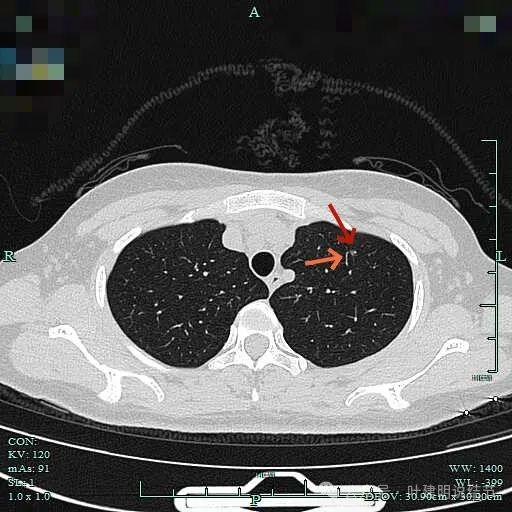

薄层上病灶出现,点状,边缘不光滑。

轮廓清,有微小血管走向病灶,表面并不光滑。

灶内密度也不均匀,微小血管走向病灶。

病灶内局部似有小空泡或局灶细支气管扩张,有血管贴边进入,整体轮廓与边界较清。